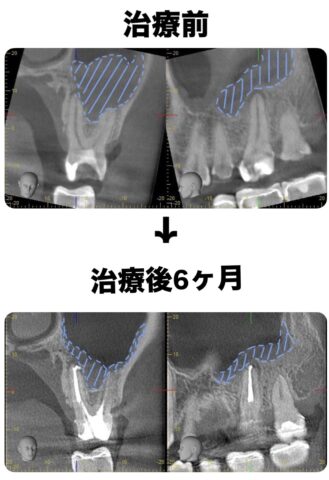

上顎洞炎マイクロスコープ診療根管治療/再根管治療

他院にて詰め物を入れたが違和感が治まらず、神経が死んでしまっていた患者様 感染根管治療にて治療

| 治療方法 |

感染根管治療 |